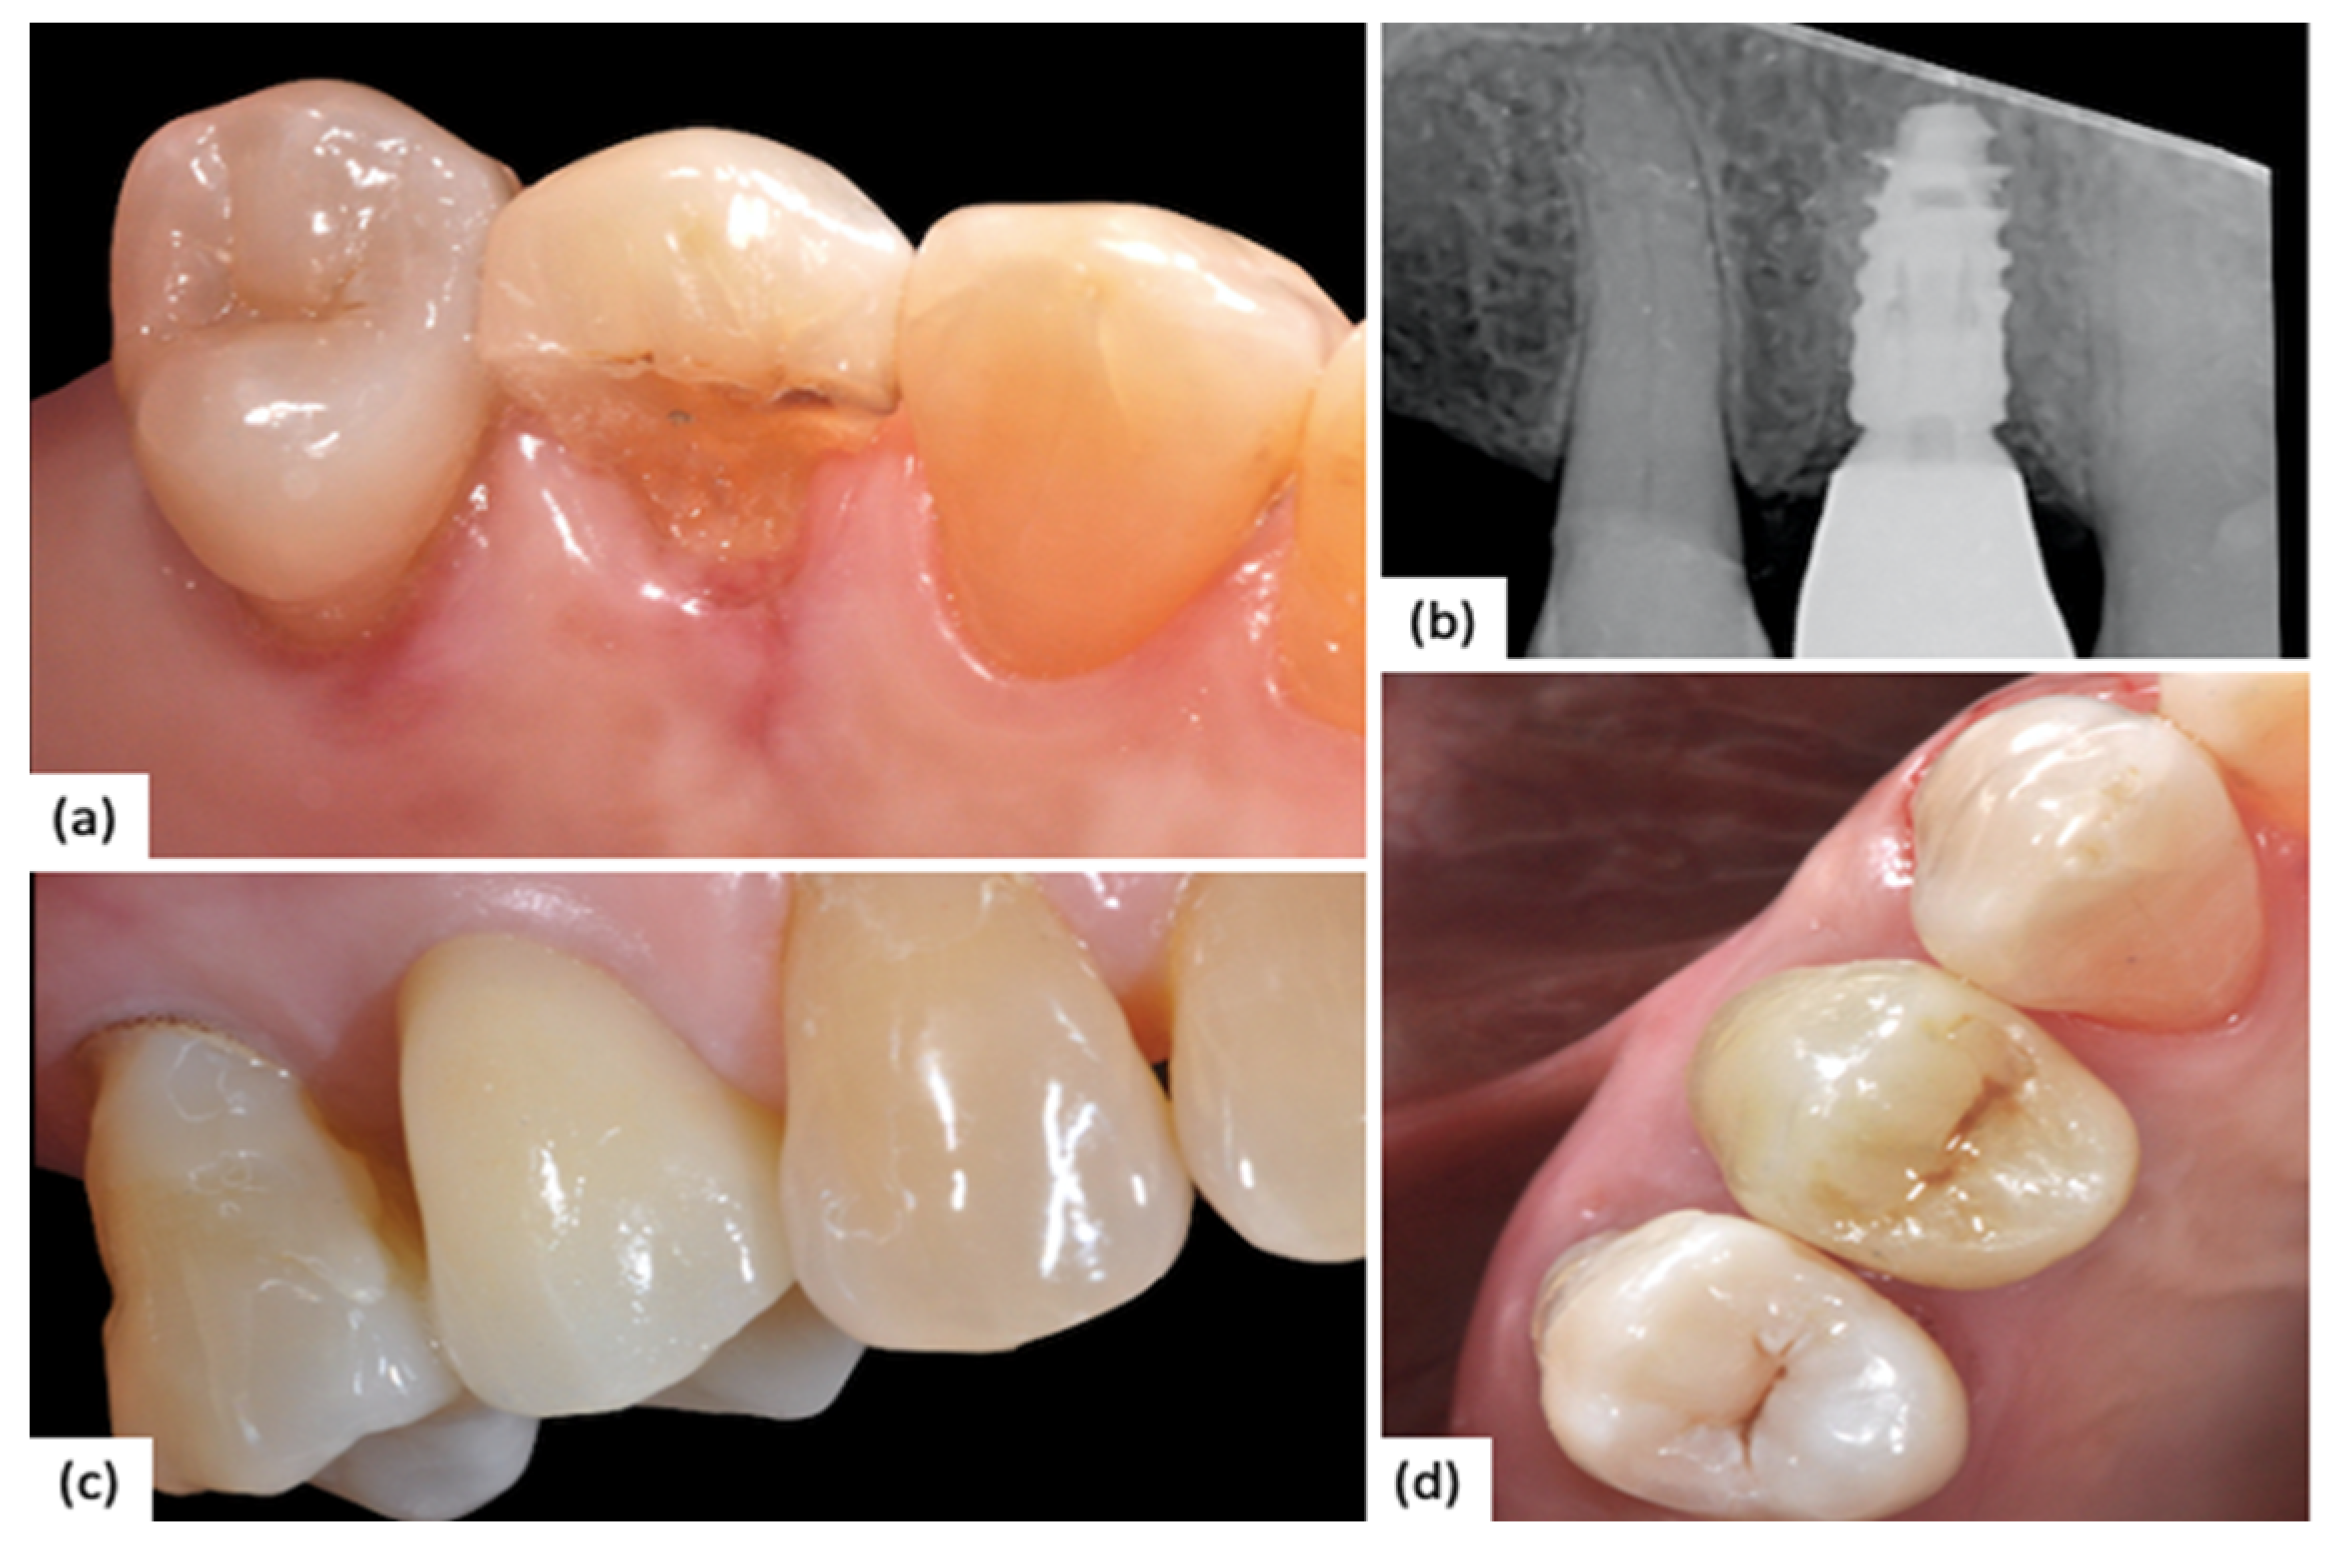

A clinical case of a 2.1 (NobelReplace) with combined digital–analog workflow is reported below (Figure 2).

Figure 2. (a) Preoperative clinical situation; (b) Peri-implant tissue after provisional conditioning; (c) Peri-implant tissue before polyvinylsiloxane impression; (d) Final restoration.